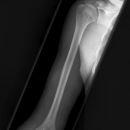

Oberarm a.-p. (1. Ebene)

Beurteilungskriterien

- Ellenbogenaxialwinkel = 162°

- Gelenkspaltbreite (Ellenbogengelenk) = 3mm